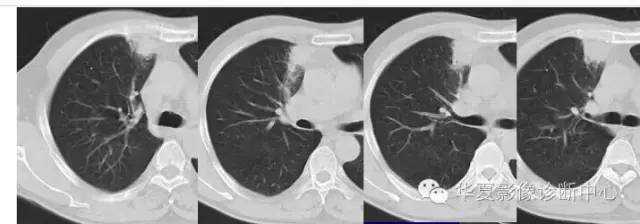

周围GGO边界清楚,分叶征、胸膜凹陷征、含气支气管,混合型GGO

首先看边缘

是否清楚

第一步:判断是否GGO

第二步:判断是否肿瘤

第三步:看边缘及内部征象

磨玻璃结节良恶性影像分析策略 混合型,边界清楚、分叶征,考虑肺癌

边界清楚,分叶征,空泡征